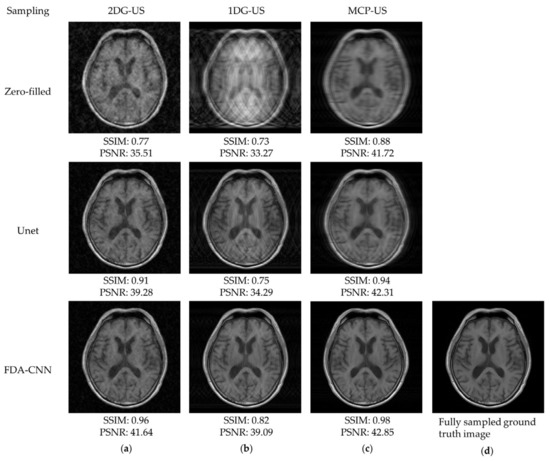

4.1. BraTs 2020-T1 Dataset